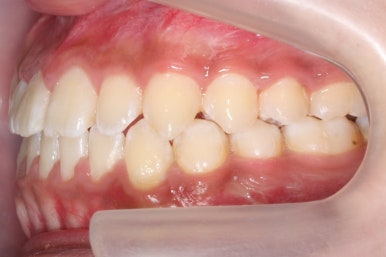

위 사진들은 부산주걱턱교정 키다리아저씨치과에 내원하셨을 당시의 입안 모습입니다.

입 안의 모습에서도 주걱턱의 특징으로는

하악이 앞으로 나와있습니다.

윗니는 뻐드러지고 아래 앞니는 뒤쪽으로 쓰러져 있습니다.

교합이 맞지 않습니다.

얼굴모습과 입 안의 못브을 종합했을 때, 양악수술을 통해 얼굴모습과 교합을 같이 개선하기로 했습니다.